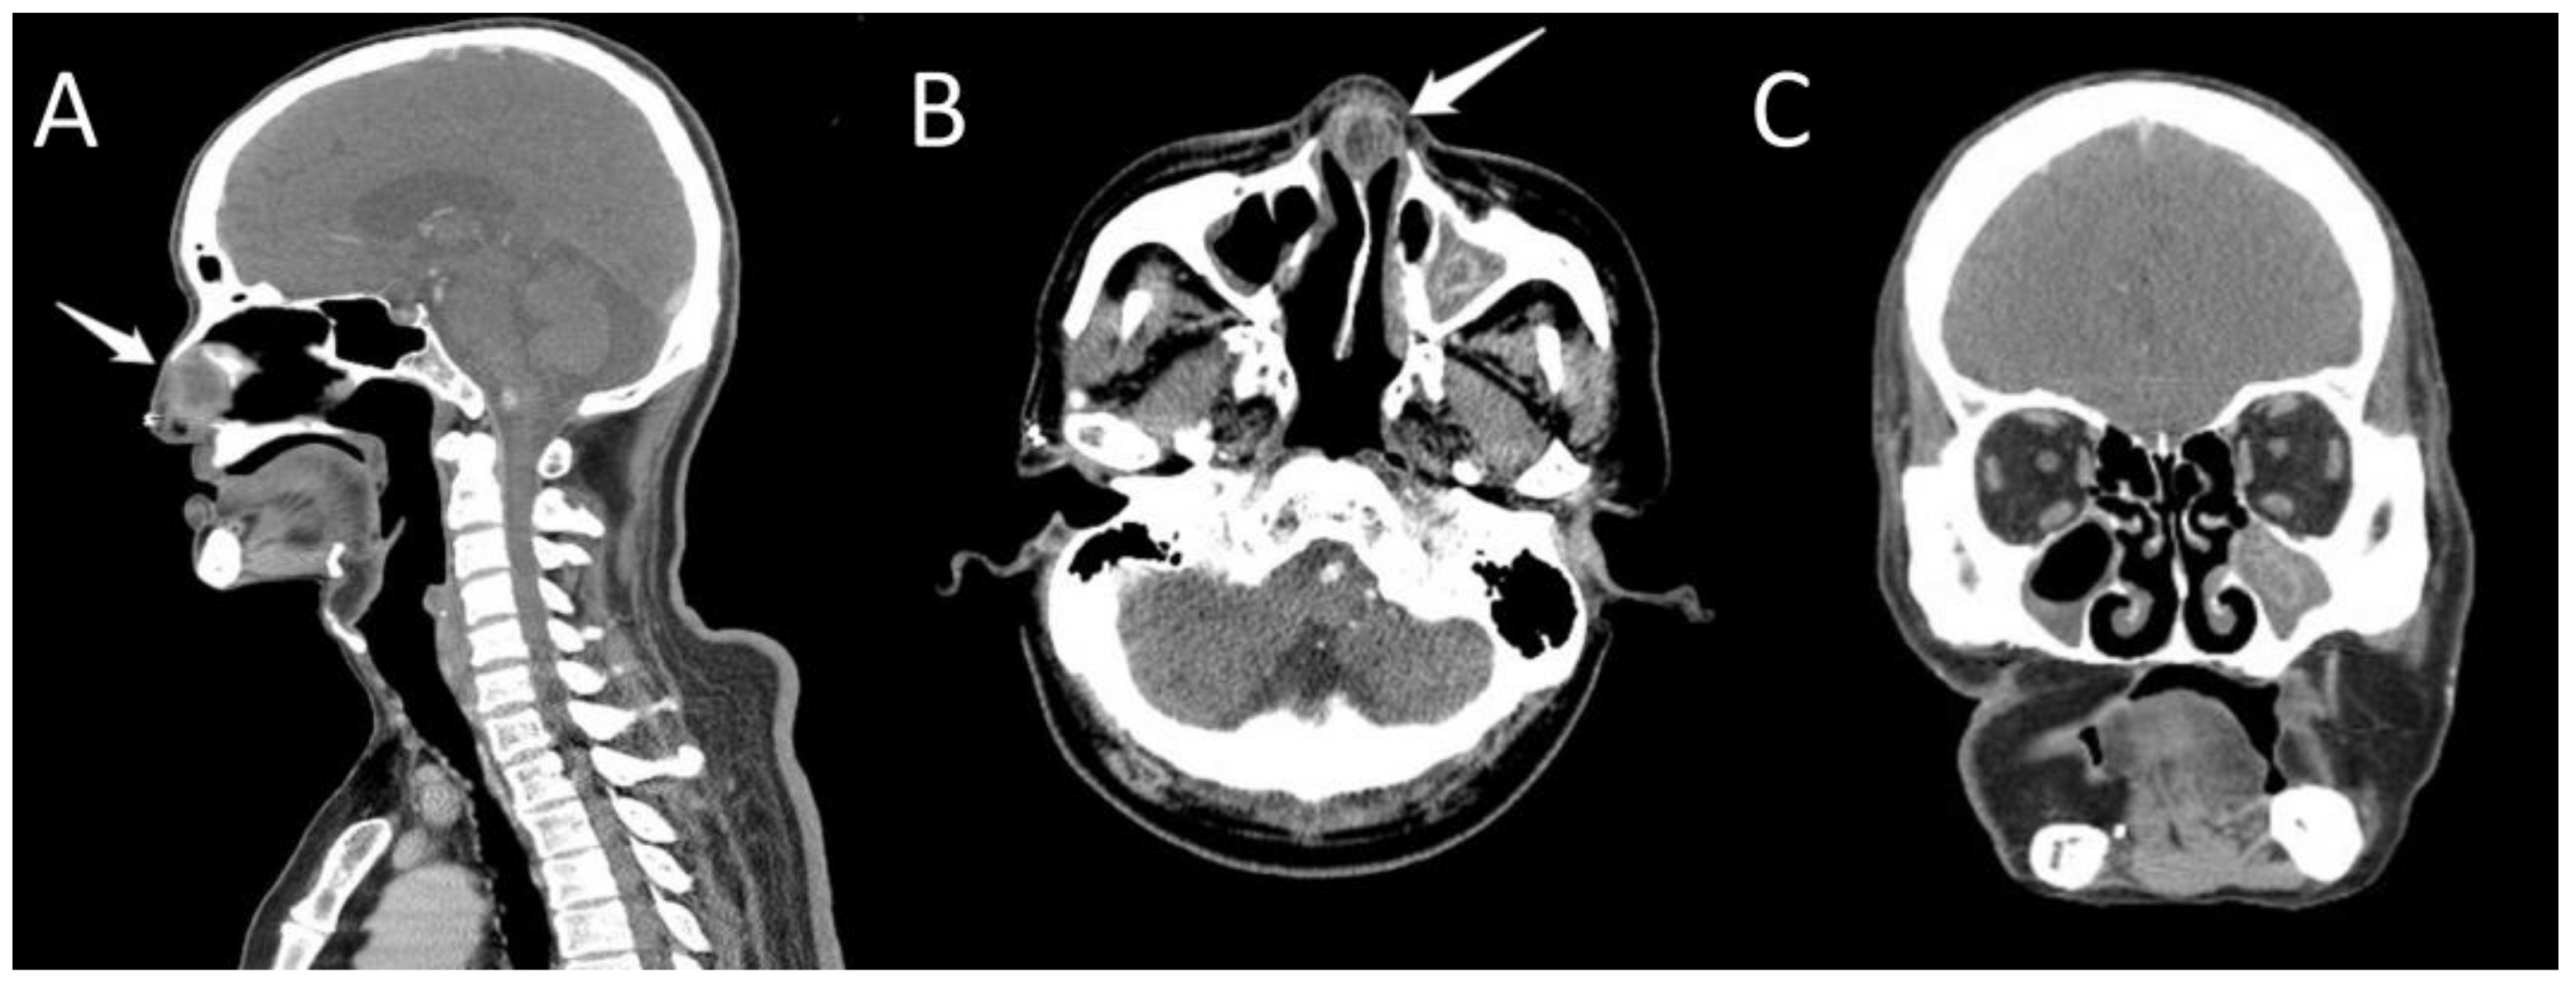

2. Case Presentation